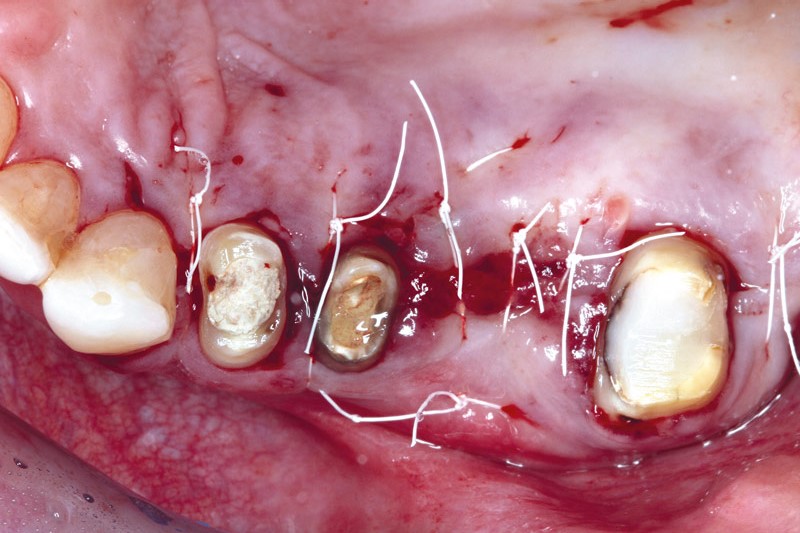

05/11 - Suturing.

Ridge augmentation using cerabone®, Jason® membrane and Straumann® Emdogain® - Dr. S. Pelekanos